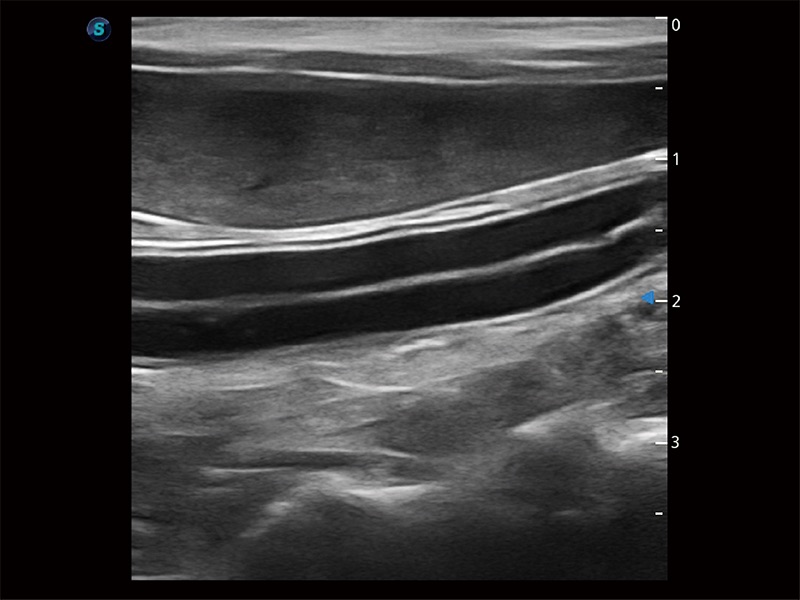

為精細(xì)結(jié)構(gòu)及組織邊緣提供高清晰度的圖像和更大的成像視野。幫助減輕醫(yī)生的用眼疲勞,快速精準(zhǔn)獲得測(cè)量的數(shù)據(jù)。